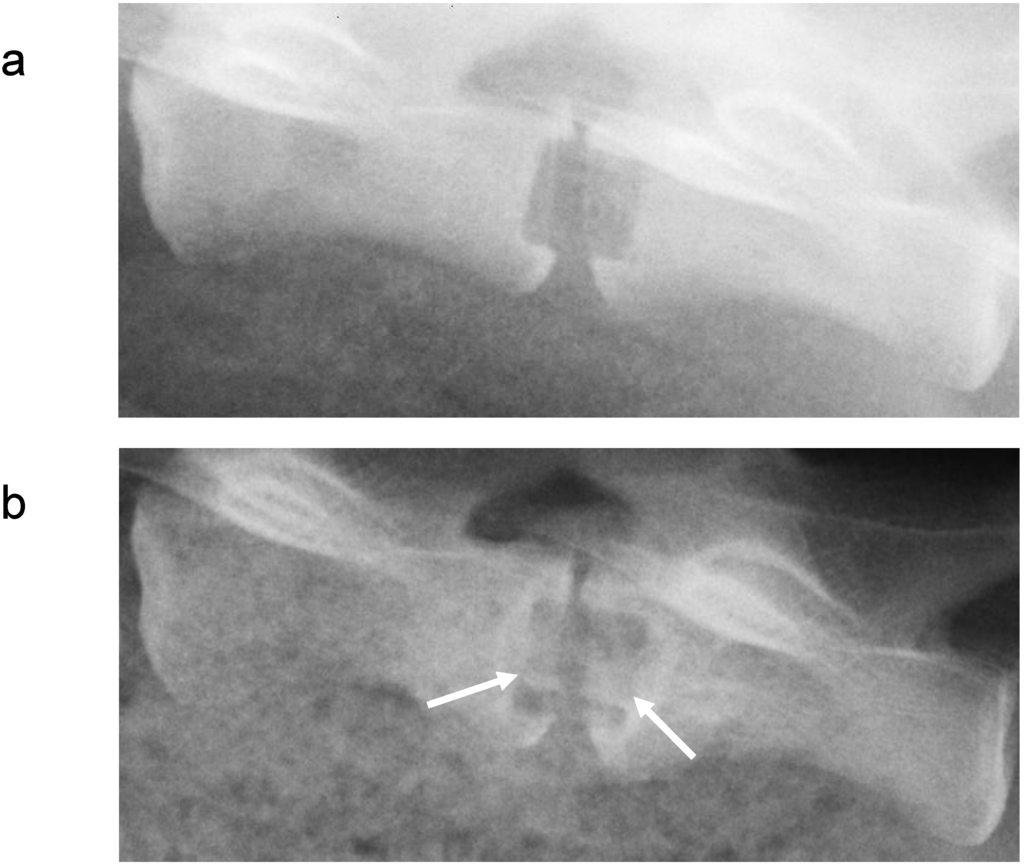

Metals and/or alloys have proven to be successful, although drawbacks do exist. In spinal surgery, amongst others, permanent materials such as metals (and non-resorbable polymers) remain susceptible to long-term complications such as migration [103], wear [61], late foreign body reaction [61,104] and infection [105]. The inflammatory reaction is, in some cases, the result of the inevitable corrosion of alloys in vivo (often referred to as particle disease), and also in the spine [106,107]. In other cases, the aforementioned micro-motion through the spinal motion segment may lead to particle debris [22]. Therefore strategies to minimize implant related problems have been devised such as removal of the implant after fulfilling its purpose in every patient [108], or to selectively remove the implant in symptomatic patients [95], which in return can cause neurovascular injury or refracture [95]. In the USA, retrieval surgeries of the spine were reported in 25-40% of the patients [109,110,111]. Furthermore, metallic spinal implants are strongly radiopaque on roentgenograms, which is the most widely used follow-up imaging after spinal surgery [112] (see Figure 3). This results in an obscured view and therefore hampered assessment of fusion, since the presence of a bony bridge throughout the spinal implant can not be seen [112,113,114,115]. Not only do metals/alloys interfere with simple x-ray films, they will therefore also interfere with computer axial tomography scanning (CAT) and cause artefacts (scattering) with magnetic resonance imaging (MRI) [100] In contrast, the presence of a bony bridge on a plain roentgenogram in radiolucent spinal implants can be visualized and does correlate with surgical exploration, considered the gold standard [116]. Radiolucent spinal implants are generally made from non-degradable polymers such as polyetheretherketone (PEEK) and will also not interfere with CAT scans or MRI scans. However, in a similar fashion as metallic cages, non-degradable cages will remain susceptible to similar long-term complications. Development of degradable spinal cages will not only result in optimal assessment of spinal fusion during follow-up using x-ray films (see Figure 4), CAT scans or MRI scans, but also avert potential long-term complications, resulting in a patient-friendly and cost-effective treatment option.

Figure 3. A postoperative lateral roentgenogram of an explanted goat spine with the placement of a radiolucent cage (a) and a titanium cage (b).